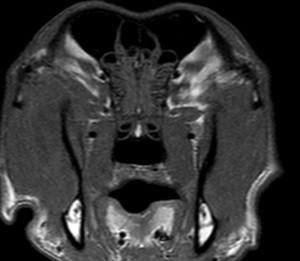

Fig 2a. Transverse T1 WI pre-contrast

Fig 2b. after administration of gadolinium of the skull. Note the contrast-enhancing lesion in the left temporal muscle